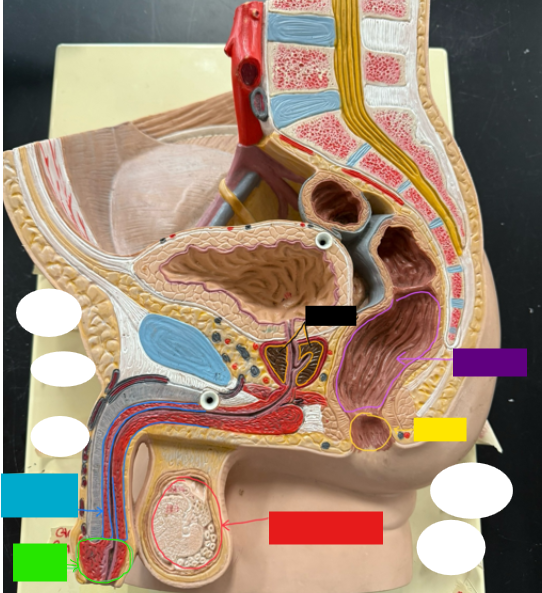

What is the name of the red box?

Ureter

What is the name of the red box?

Vas deferens

What is the name of the yellow box?

Seminal vesicle

What is the name of the blue box?

Prostate

What is the name of the light green box?

Epididymis

What is the name of the light blue box?

Prepuce

What is the name of the blue box?

Corpus spongiosum

What is the name of the light green box?

Glans penis

What is the name of the red box?

Seminiferous tubules

What is the name of the black box? X2

Prostate

What is the name of the purple box?

Rectum

What is the name of the yellow box?

Anus

What is the name of the red box?

Scrotum

What is the name of the orange box?

Corpus cavernosum

What is the name of the light blue box?

Spongy urethra

What is the name of the red box?

Prostatic urethra

What is the name of the pink box?

Ejaculatory duct

What is the name of the yellow box?

Membranous urethra

What is the name of the brown box?

Testis